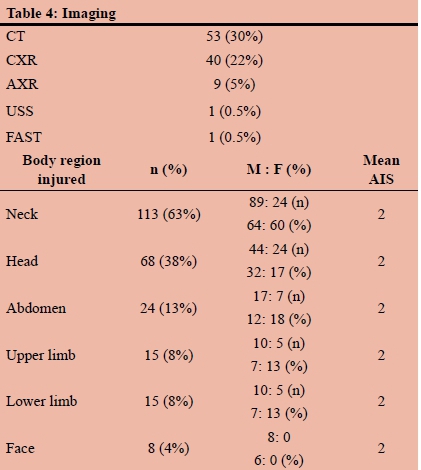

RESULTS: During the five-year study period, a total of 179 patients were included. The mean age was 29 years (SD12) and there were 139 (77%) males and 40 (23%) females. Of these, 16 had a previously established psychiatric diagnosis and two had a prior history of having sustained self-harm. The previously diagnosed psychiatric illnesses included mood dysphoria disorders (5), schizophrenia (3), substance abuse and dependency (1), anti-social personality disorder (1) and unspecified (6). The mechanism was penetrating trauma in 47 (26%). The penetrating mechanisms included stab wounds (SW) in 33, gunshot wounds (GSW) in 10, broken glass in 2 and a single impalement. Blunt mechanisms accounted for the remaining 131 (73%) injuries. The most common mechanism of blunt self-harm was hanging in 101 patients. This was followed by vehicular related trauma (8), jumping in front of a train (1) and jumping from a height (1). In 17 patients the exact mechanism of the blunt trauma was unclear. There was no statistical difference in the mechanism of injury between male and female patients. There were 38 (28%) men and 9 (23%) women who sustained a penetrating injury and there were 100 (72%) male and 31 (78%) female patients who had a blunt mechanism of injury. A total of 53 CT scans were obtained, 40 chest X-rays, 9 abdominal X-rays and 2 ultrasounds. There were 113 neck injuries, 68 head injuries, 24 abdominal injuries, 15 upper limb and 15 lower limb injuries and four facial injuries. A total of 32 operations were performed. These included laparotomy (14), neck exploration (5), tracheostomy (4). A total of 22 patients developed a complication

A total of 53 CT scans were obtained, 40 chest X-rays, 9 abdominal X-rays and 2 ultrasounds. Table 4 tabulates these investigations. There were 113 neck injuries, 68 head injuries, 24 abdominal injuries, 15 upper limb and 15 lower limb injuries and four facial injuries. A total of 32 operations were performed. These included laparotomy (14), neck exploration (5), and tracheostomy (4). The remainder are listed in Table 5. A total of 22 patients developed a complication. These are broken down in Table 5. A total of 4.5% of patients required ICU admission and the overall mortality rate was 2.5%. Figure 1 demonstrates a self-inflicted laceration of the neck in an acutely psychotic patient. This required a neck exploration and ligation of a severed internal jugular vein and reconstruction of the injured larynx. Figure 2 is the CT scan of a man who shot himself in the face. He survived the injury and required extensive reconstructive surgery.